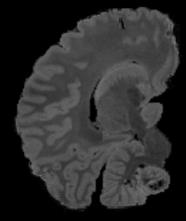

In neuroimaging, MRI tissue properties characterize underlying neurobiology, provide quantitative biomarkers for neurological disease detection and analysis, and can be used to synthesize arbitrary MRI contrasts. Estimating tissue properties from a single scan session using a protocol available on all clinical scanners promises to reduce scan time and cost, enable quantitative analysis in routine clinical scans and provide scan-independent biomarkers of disease. However, existing tissue properties estimation methods - most often $\mathbf{T_1}$ relaxation, $\mathbf{T_2^*}$ relaxation, and proton density ($\mathbf{PD}$) - require data from multiple scan sessions and cannot estimate all properties from a single clinically available MRI protocol such as the multiecho MRI scan. In addition, the widespread use of non-standard acquisition parameters across clinical imaging sites require estimation methods that can generalize across varying scanner parameters. However, existing learning methods are acquisition protocol specific and cannot estimate from heterogenous clinical data from different imaging sites. In this work we propose an unsupervised deep-learning strategy that employs MRI physics to estimate all three tissue properties from a single multiecho MRI scan session, and generalizes across varying acquisition parameters. The proposed strategy optimizes accurate synthesis of new MRI contrasts from estimated latent tissue properties, enabling unsupervised training, we also employ random acquisition parameters during training to achieve acquisition generalization. We provide the first demonstration of estimating all tissue properties from a single multiecho scan session. We demonstrate improved accuracy and generalizability for tissue property estimation and MRI synthesis.